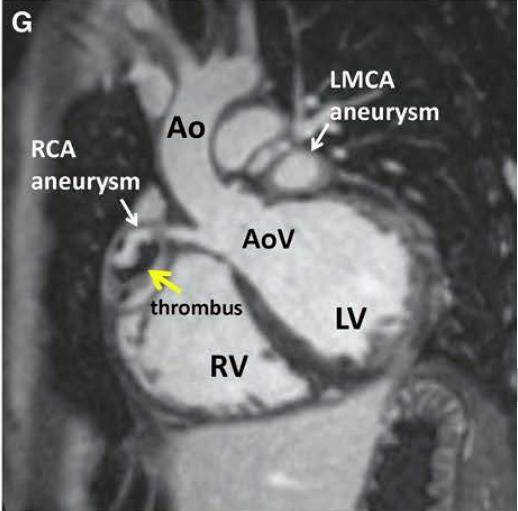

6岁儿童的川崎病的冠状动脉造影图,巨大冠状动脉瘤,参考6

磁共振呈像,白色箭头所指冠状动脉瘤,参考1

建议所有的川崎病患者应行:超声心动图、心电图检查。如果超声心动图不能充分显示冠状动脉,则使用超高速计算机断层扫描血管造影(computed tomographic angiography, CTA)、磁共振血管成像(magnetic resonance angiography, MRA)充分呈现冠状动脉树。